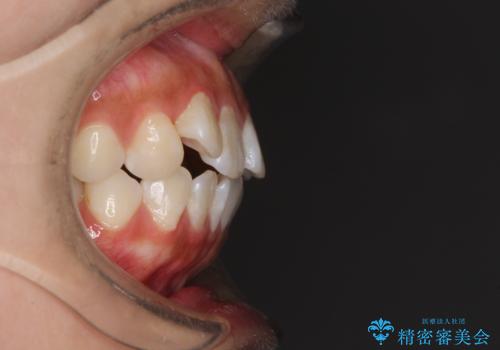

前歯のデコボコが気になる インビザラインによる矯正治療

- 上下前歯のデコボコを気にして来院された患者様です。

インビザラインによる上下歯列の拡大と、IPR(歯と歯の間を削る)にるスペースの獲得により、前歯のデコボコを改善することとしました。